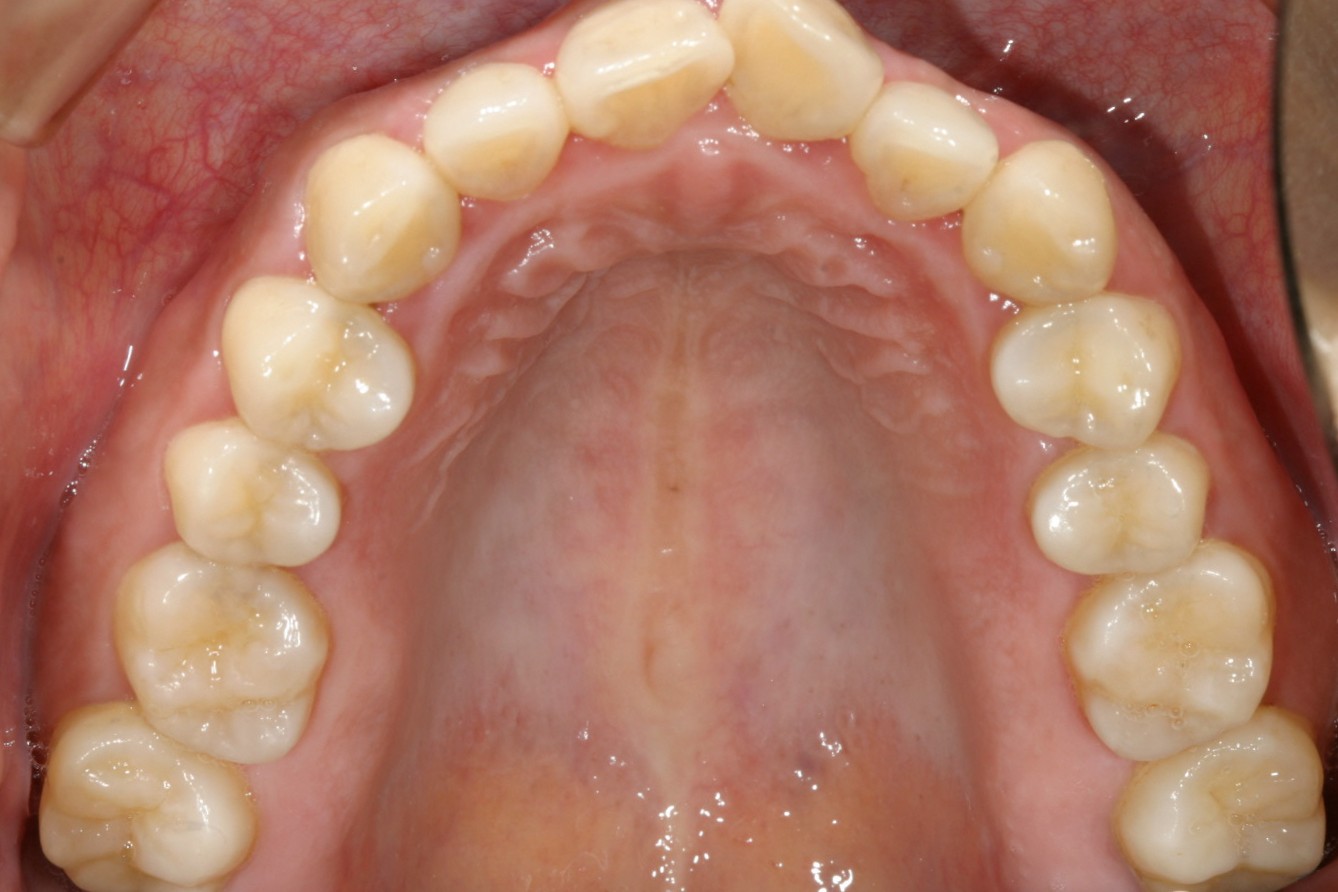

上顎前歯に叢生が見られます。

綺麗に整列出来ました。